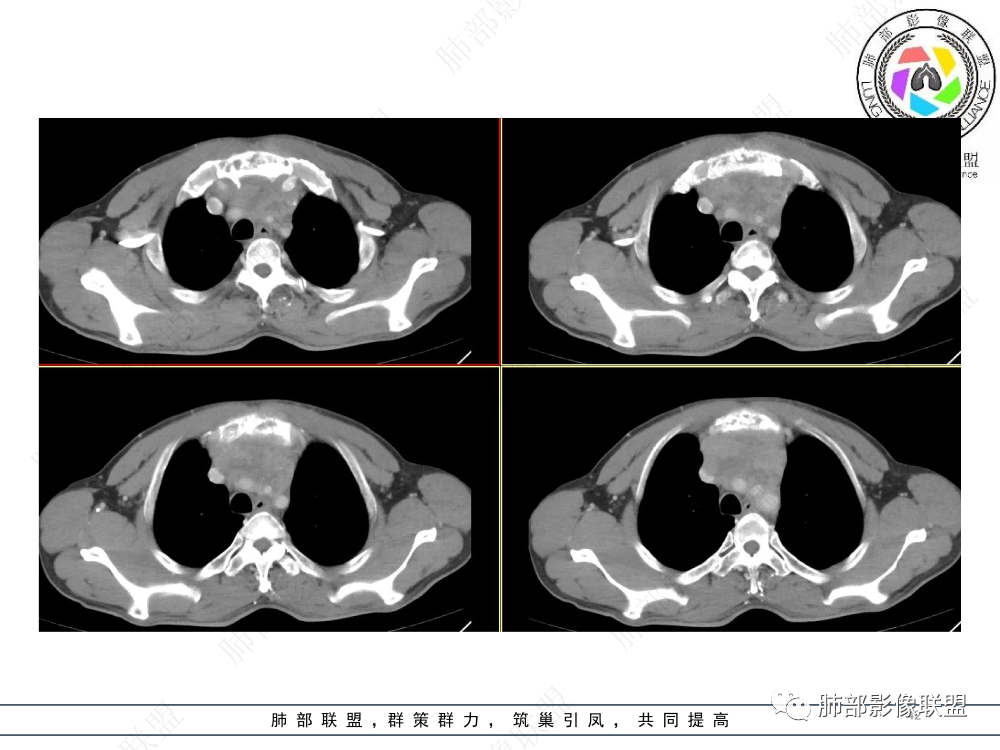

1.临床资料:中老年男性,病史较长-8个月,主诉胸痛,实验室资料:乳酸脱氢酶(LDH)升高。

2.影像表现:前上纵隔较大肿块,密度不均,形态不规则,边界不清,有结节样突起,脂肪间隙显示不清。病灶侵犯左无名静脉及上腔静脉,其中左无名静脉闭塞(胸背部侧支循环明显,亦表明回流受阻)。增强后轻中度不均强化。坏死边界欠清晰。可见心包积液,提示心包受侵犯。右侧上叶及纵隔胸膜下结节影,疑胸膜肺转移可能。胸骨柄后缘皮质不完整,疑骨质破坏(未提供骨窗及矢状位图像)。左锁骨上可见肿大淋巴结。